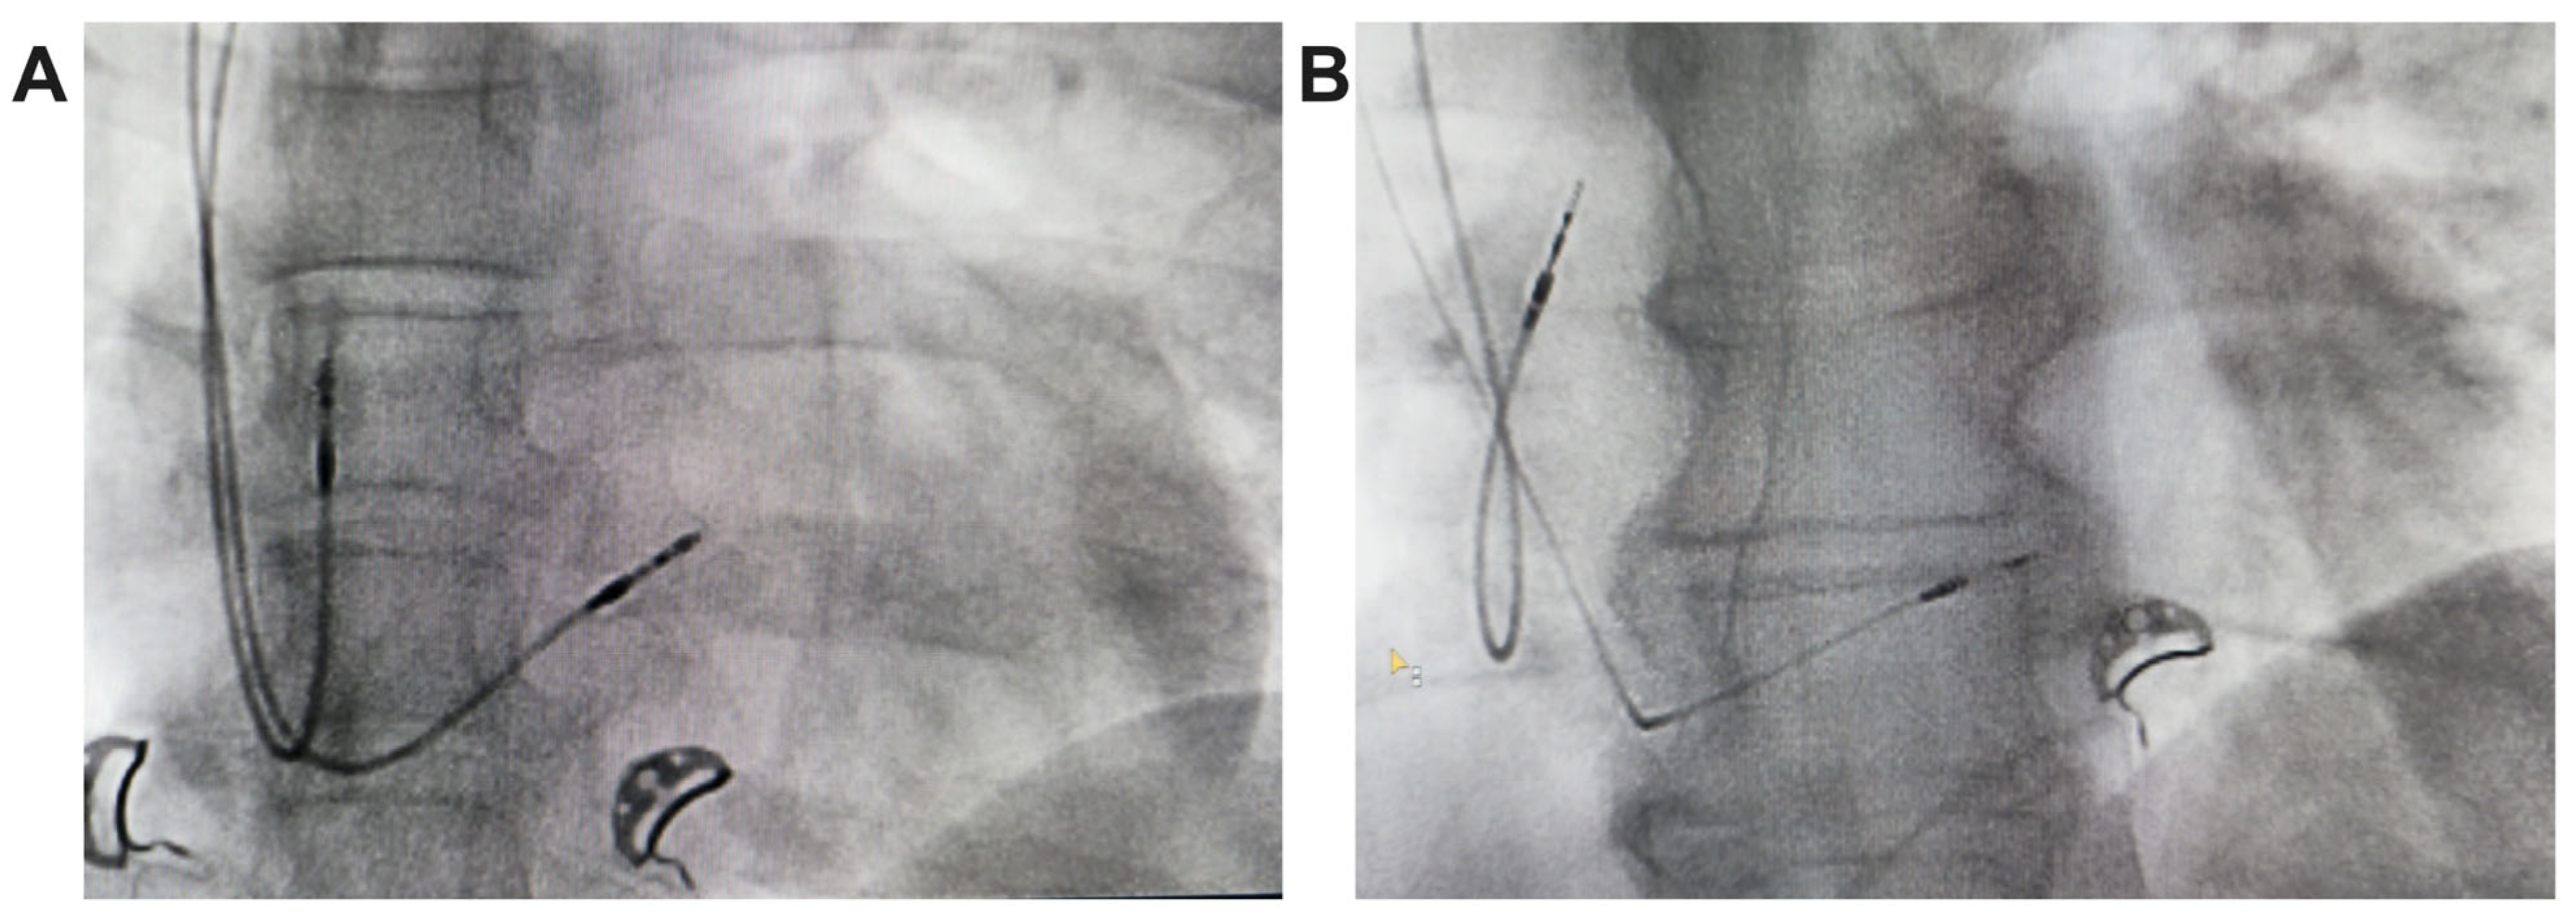

2.2. Implant Procedure